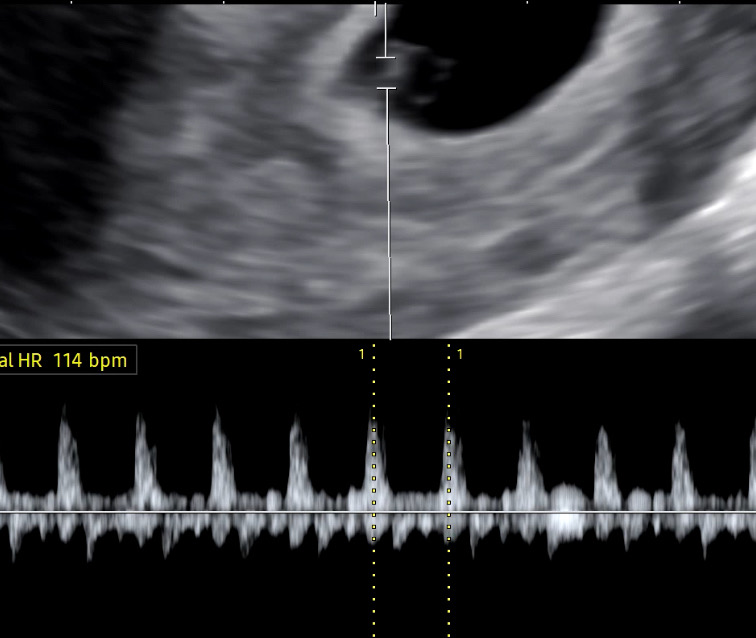

6주차(?) 심장소리

2주일 기다리는 거 못참고 분만병원 뚫을 겸 일주일 만에 갔습니다. 주수가 줄어들었어요(?) 선생님은 그럴 수 있다고 하더라구요. 어쨌든 오늘 아가 심장소리도 들었어요… 깨알 싸이즈가 심장이 뛴다니… 소리듣고 울었습니다.ㅠㅠ 잘만 자라준다면 뭐든 견디겠어요…